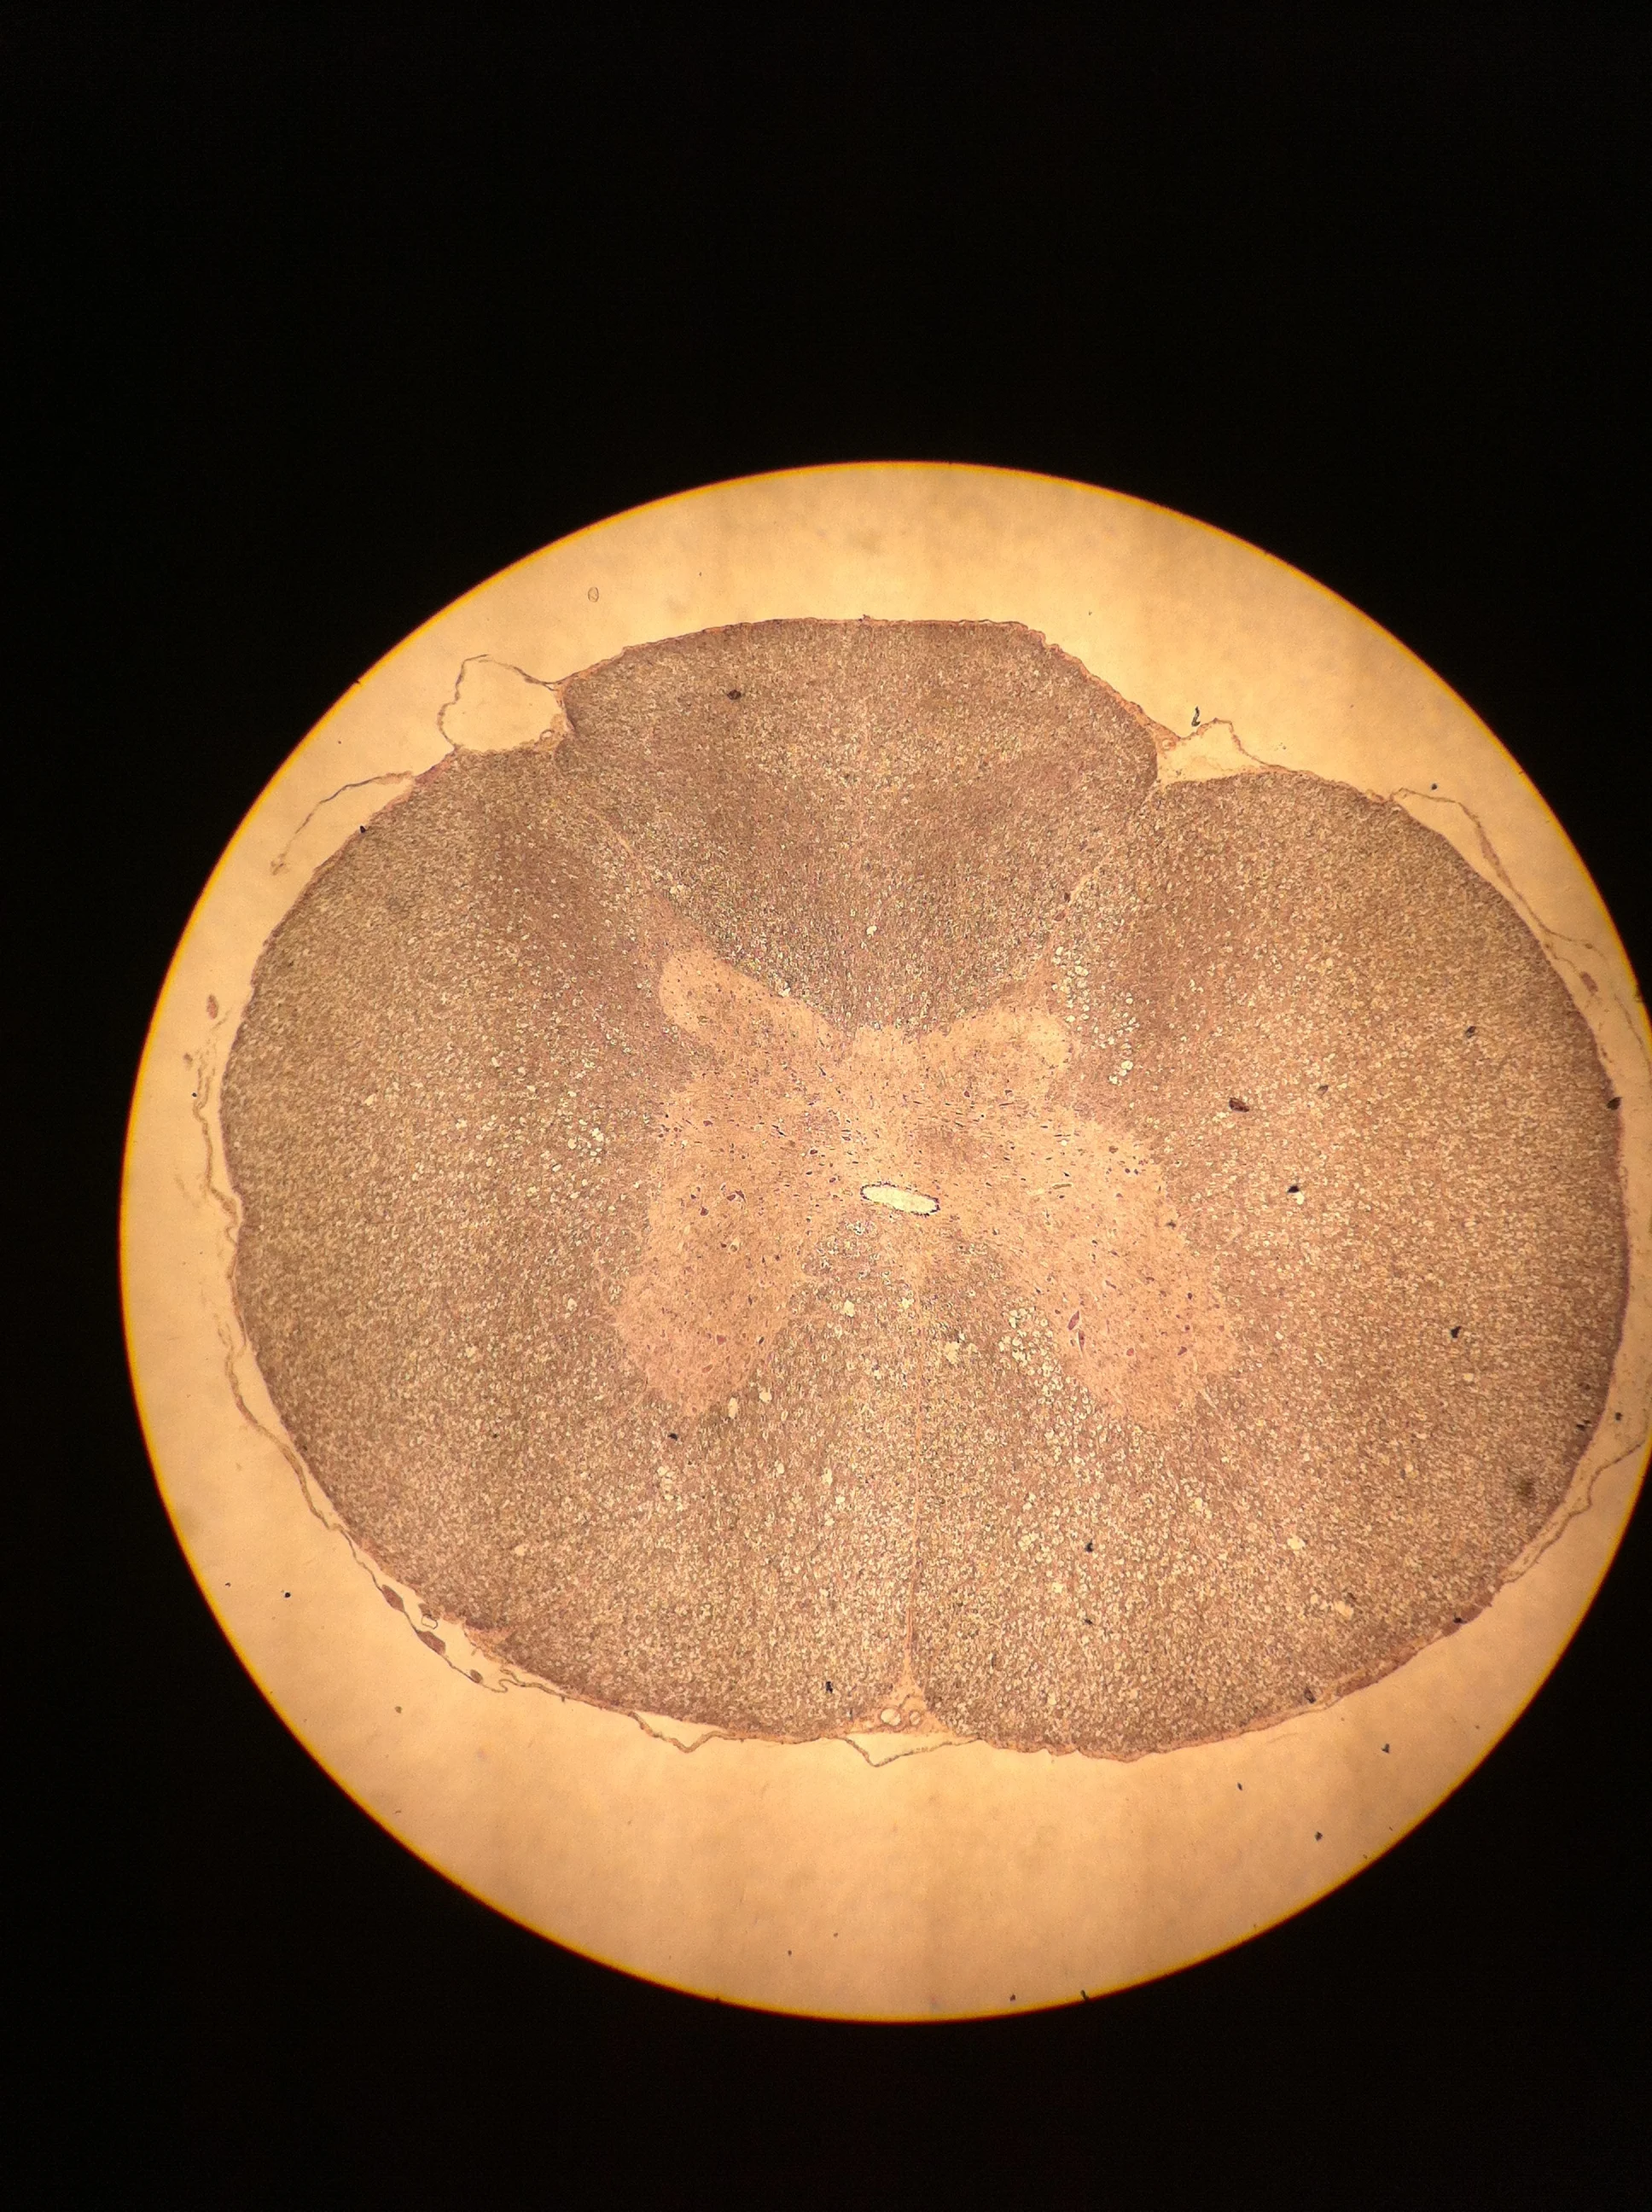

Thoracic Spine 40X